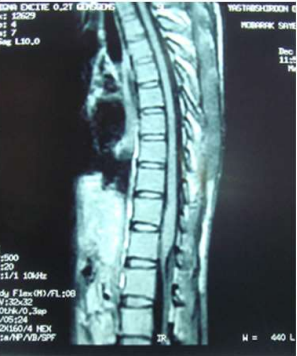

Image (1 & 2) Sagittal MRI of the spine of case (1) showing cauda eguia expansion and hyperintense patches of in the cauda equine of both T1 and T2 weighted MRI

Eight of the ten patients were diagnosed utilizing MRI which showed Dorsal 12 to Lumber 1 or 2 spinal cord swelling with hyper intense patches in T2 images , while the remaining two patient were diagnosed utilizing CT myelogram which showed Dorsal 12 to Lumber 1 or 2 spinal cord swelling.

Magnetic resonance imaging in spinal schistosomiasis usually shows swollen conus and epiconus beside areas of hyper-signal in T2 and heterogeneous contrast enhancement[12]. Multinodular intramedullary contrast enhancement of the distal cord allowed accurate preoperative MR imaging diagnosis of spinal schistosomiasis[12]. Cerebrospinal fluid (CSF) may show changes in spinal schistosomiasis. Characteristic features are mild to moderate pleocytosis, presence of eosinophils, slight to moderate protein increase, elevated gamma globulin concentration and a positive immune assay. These abnormalities are not always, accidentally schistosomal ovae may appear in the cerebrospinal fluid [13].